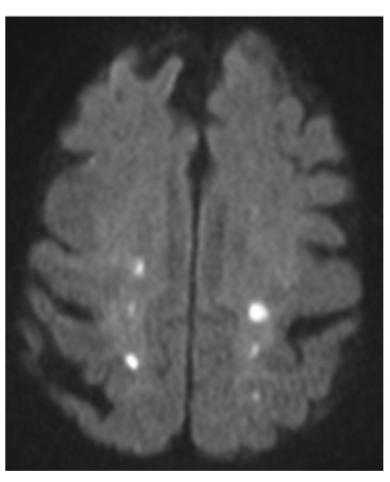

22

Q

The punctate stroke shown in the provide image is suggestive of what etiological cause?

A

cardioembolic etiology